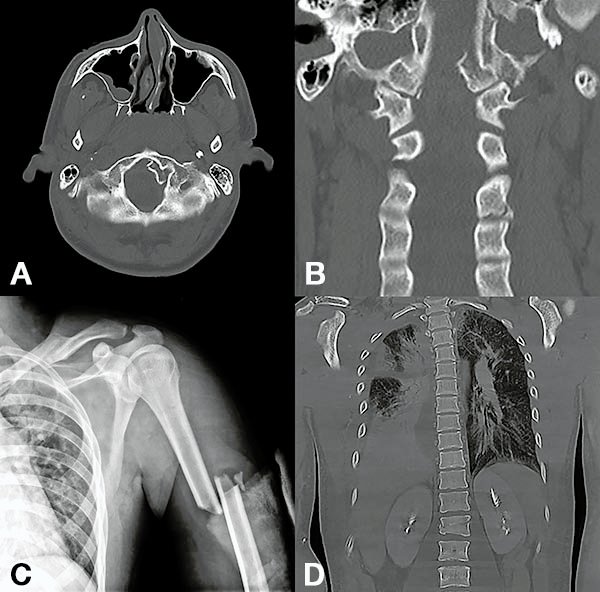

Figura 1:

Caso 24. Hombre 21 años con politraumatismo por accidente vial. A y B: Fractura del cóndilo occipital izquierdo. C: Fractura expuesta del húmero izquierdo y clavícula. D: Contusión pulmonar más hemotórax derecho.

Figura 2:

Caso 24. A y B: Fractura horizontal que compromete cuerpo, pedículo izquierdo y apófisis espinosa de L1 (L1: B1; N1 AOSpine). C y D: Estabilización percutánea T12-L2.

Figura 3:

Caso 24. A: Fractura L1: B1; N1. B: Control 7 meses que evidencia consolidación. C y D: Retiro de osteosíntesis a los 9 meses con buena movilidad en las radiografías dinámicas de control.